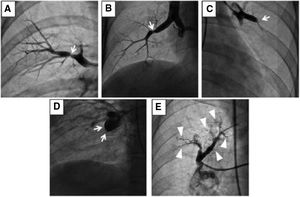

Biplanar digital subtraction angiography (DSA)11 and electrocardiography (ECG)-gated computed tomography pulmonary angiography (CTPA)12 are both used to characterize vessel morphology, the types of lesions (ring-like stenosis, web, subtotal, total occlusions or tortuous lesions – Figure 1) and location of thrombi in the main, lobar, or segmental pulmonary arteries.13 CTPA gives us complementary information about the presence of bronchial collateral arteries (which can correlate with more central disease14), lung parenchyma and mediastinum.12

Angiographic classification of CTEPH lesions.

(A) Type A: ring-like stenosis lesion. (B) Type B: web lesion. (C) Type C: subtotal lesion. (D) Type D: total occlusion lesion. (E) Type E: tortuous lesion. From A to E increases the complexity of BPA; decreasing the success rate and increasing the likelihood of complications.

Reprinted with permission from Kawakami et al. Circ Cardiovasc Interv 2016;9:e003318.